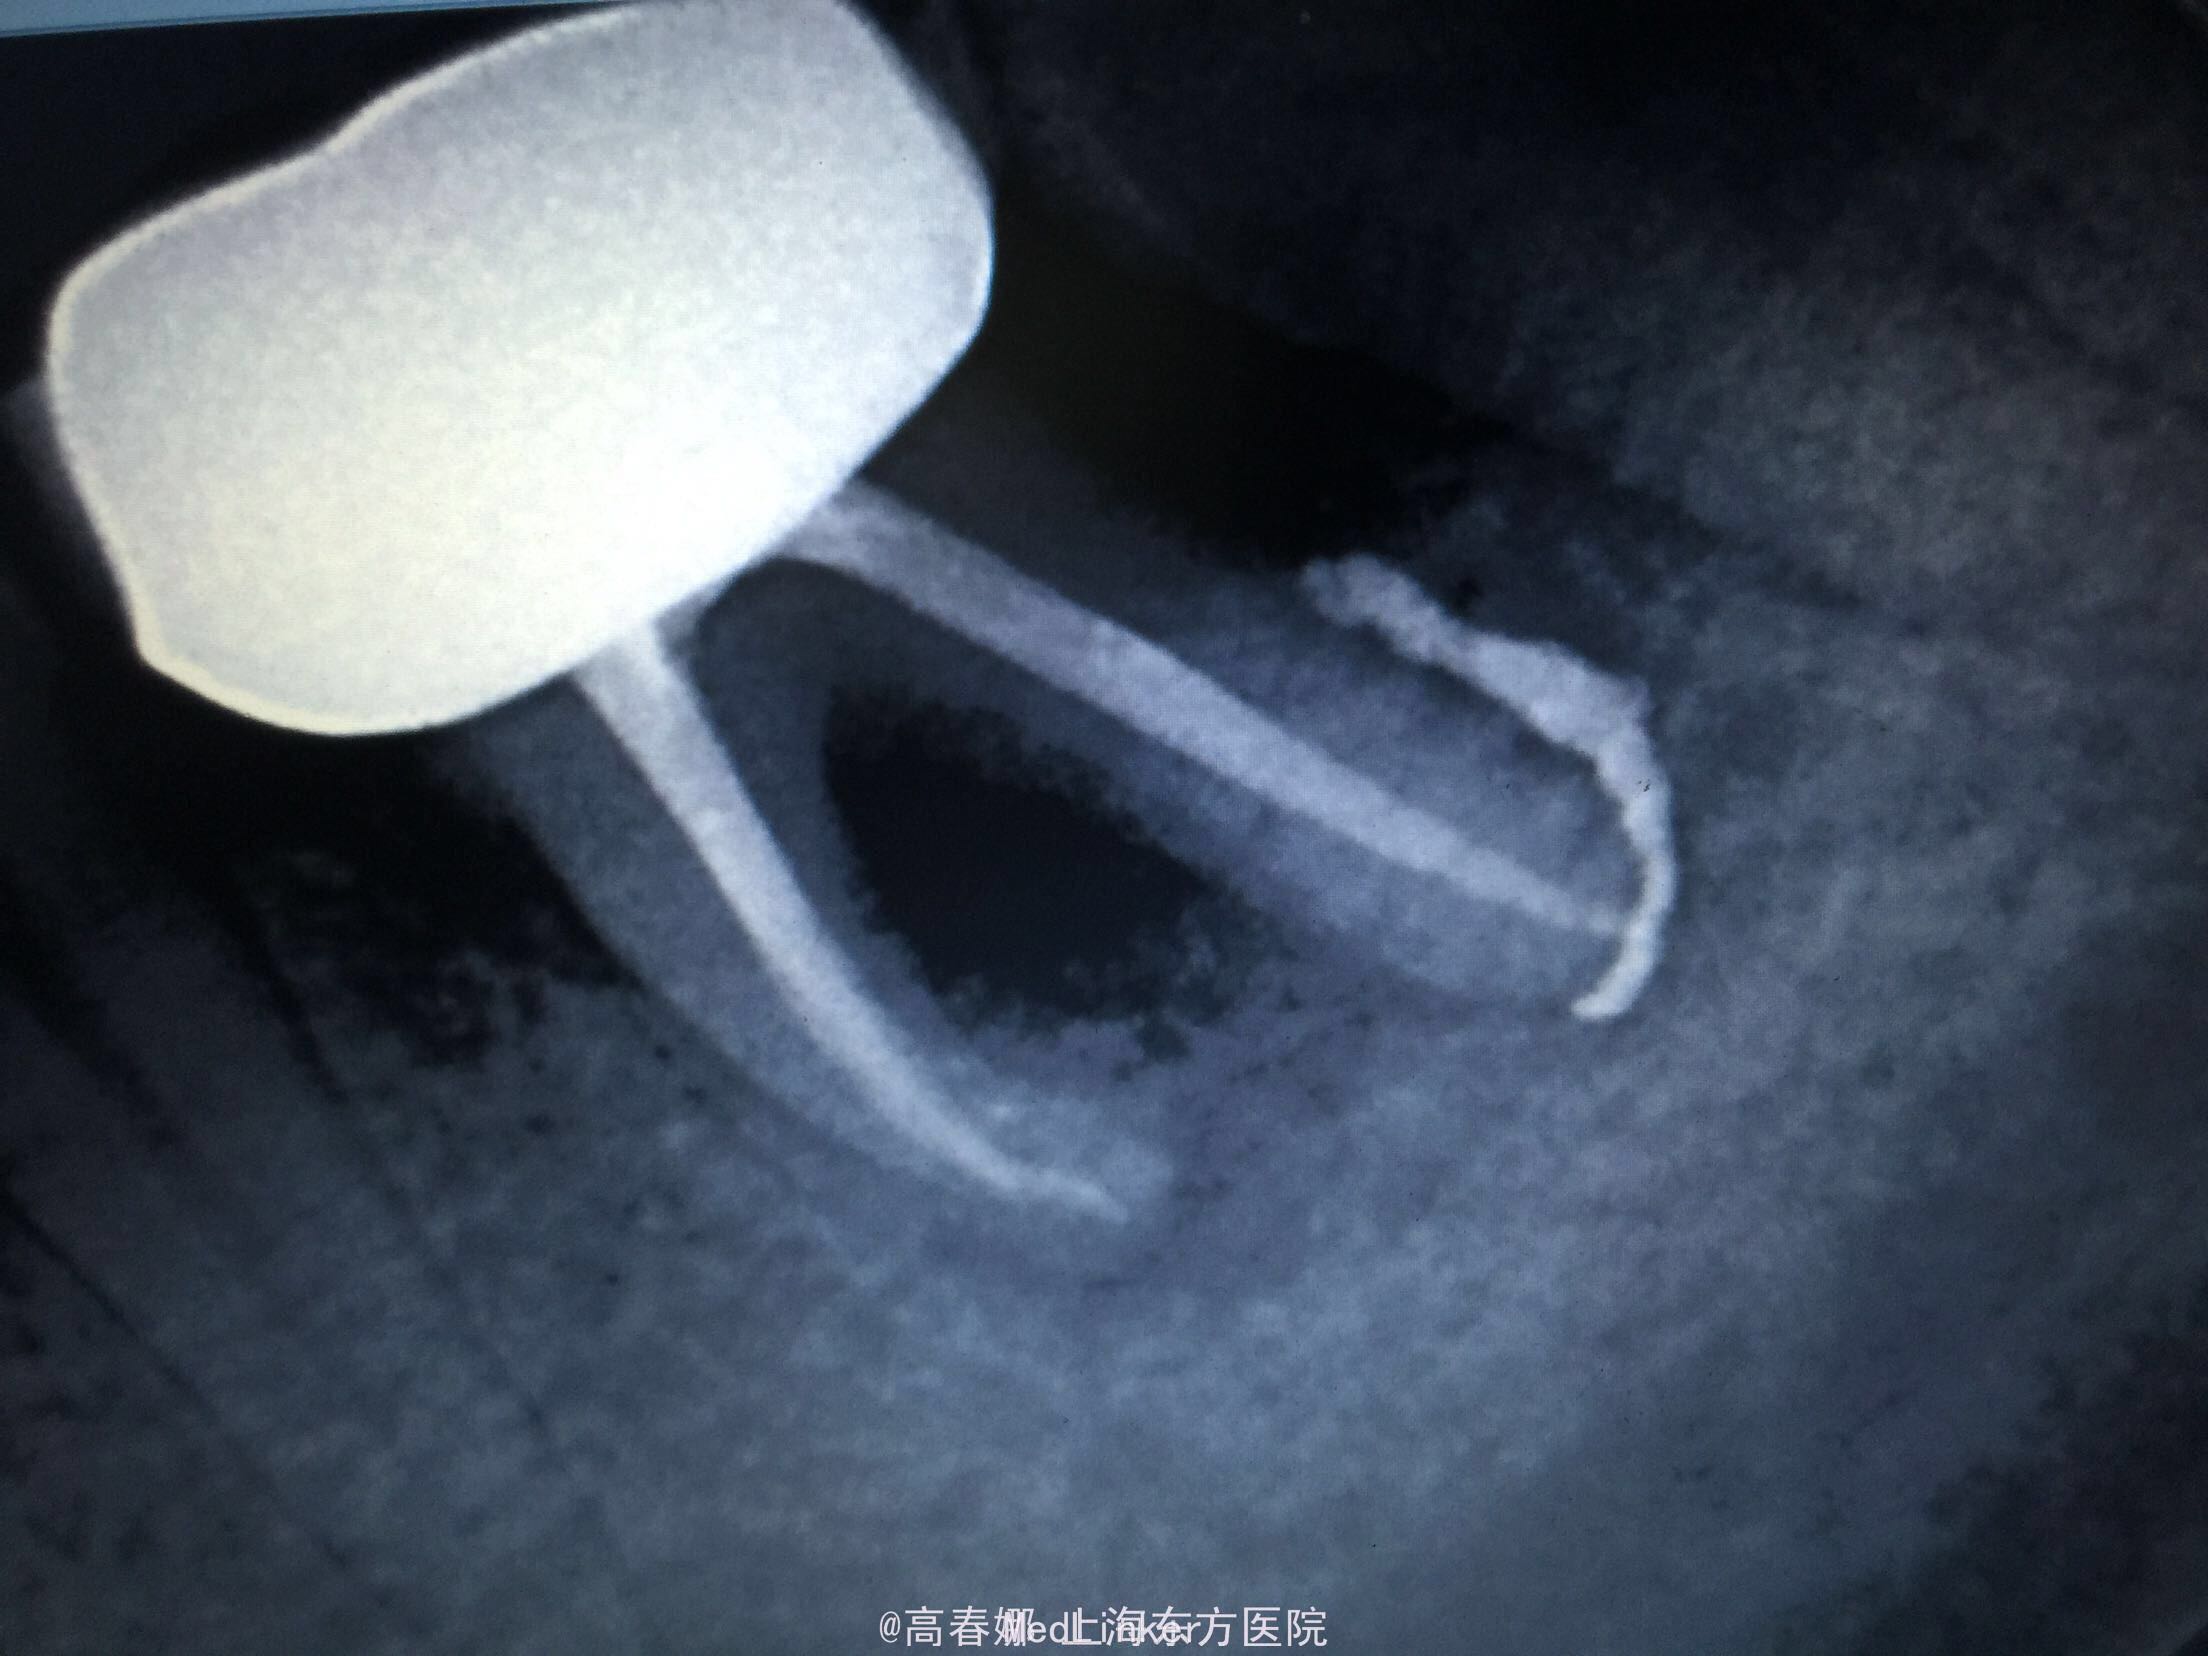

检查:36冠修复,叩诊(+-),松动II度,颊侧牙龈瘘管,牙周袋约3mm,根分叉未探及,冷(-)。 X线示:36根尖区及根分叉区大面积阴影。

诊断:36牙周牙髓联合病变 治疗:告知患者36预后差,治疗效果不理想,如炎症控制不好拔牙可能,患者要求试着保留患牙。 36拟行完善RCT及牙周刮治术,观察根尖区及根分叉愈合情况。 36常规根管治疗后行牙周刮治术,术后牙龈瘘管消失。

随访:三个月复查,牙龈未见明显红肿及瘘管,36扣痛无,松动物。X线示:36根尖及根分叉骨密度增高。